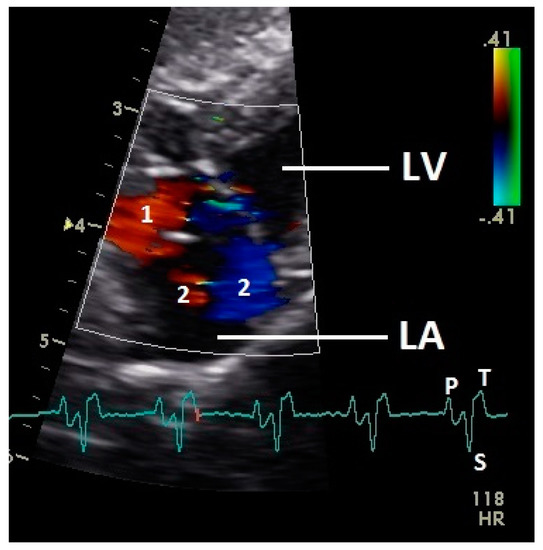

3.3. Left Atrial Filling

After the P wave of the ECG in the phase of the relaxation of myocardium of the left atrium, a little blue filling signal over the AV valve was seen in the some pigeons (n = 27; 62.8%) with the used settings (Figure 5). In all pigeons a later and faster blue inflow signal in the atrium in the time of the descending part of the T wave was recorded over the AV valve to the left part of the atrium (significant difference Chi-squared test p ≤ 0.001). At the same time a red signal was seen right and left from the valva pulmonis in some pigeons (25 out of 43 birds; 58.1%; Figure 6). The position of the valva pulmonis was almost constant in diastole (Figure 7) and systole (Figure 5 and Figure 6).

Figure 5.

Color Doppler image of the early blood inflow in the left atrium (red and blue signal). LV: left ventricle; LA: left atrium; HR: heart rate. Electrocardiogram: P: P wave, S: S wave, T: T wave. The color scale on the right of the image is calibrated in m s−1.

Figure 6.

Color Doppler image of the late blood inflow in the left atrium (red signal; 1) and blood flow vortex formation (2). LV: left ventricle; LA: left atrium; HR: heart rate. Electrocardiogram: P: P wave, S: S wave, T: T wave. The color scale on the right of the image is calibrated in m s−1.